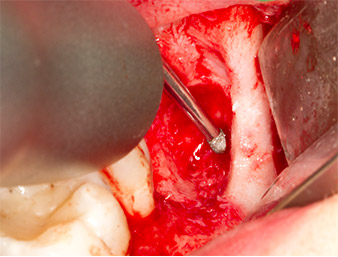

Imagen 6: Con un inserto esférico diamantado (Piezomed S2) el resto radicular se preparó de forma libre con cuidado y los bordes óseos se alisaron.

resto radicular 38

Imagen 7: El resto radicular 38 aparece bien representado en su alvéolo para extraerlo a continuación.

Con el fin de preparar el resto radicular de forma libre sin dañar el tejido, se utilizó otro inserto (Piezomed S2), que está indicado sobre todo para la preparación de la ventana lateral en los aumentos de la base del seno maxilar. Además, se utilizó la esfera diamantada para alisar los bordes óseos afilados (figuras 6 y 7). Todos los accesorios Piezomed se utilizaron con el ajuste estándar automático correspondiente sin función de refuerzo de la potencia.